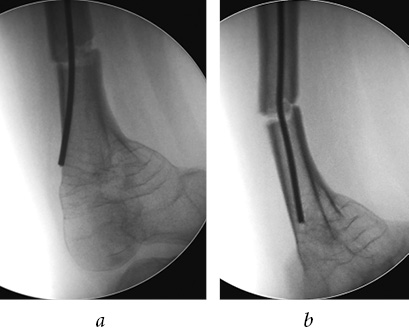

After the end of immobilization of the left lower extremity, the patient complained of a persistent restriction of movement in the left knee joint. After 2 months, control radiographs revealed TEN migration to the proximal tibial metaepiphysis (Fig. 7), which caused the blockade of the knee joint and indicated the need for a repeated surgical intervention. The patient complained of pain in the medial regions of the right knee joint during movements. The absolute stability provided by the cancellous screws in the area of the splitting of the left femoral condyles created the conditions for complete consolidation of fracture and an absence of secondary displacement. The fracture of the right femur was also consolidated.

Fig. 7. Radiographs of the left femur: a — frontal view; b — lateral view: migration of TEN into the proximal tibial epiphysial cartilage, delayed consolidation

On June 29, 2016, the child was hospitalized at the EMC for surgical treatment. Upon examination, a persistent restriction of movement in the left knee was revealed. The range of motion in the right knee joint was 5–0–105°, and pain during movements was localized in the projection of the end of the medial TEN.

After the standard preoperative examination, surgical treatment was performed on the same day. To eliminate the blockade for the knee joint, the TEN was removed. Due to the pronounced displacement of fragments of the distal third of femur, comminuted nature of the fracture, and delayed consolidation, a mini-invasive osteosynthesis with a metaphysical plate 3.5 LCP was performed to ensure adequate reposition, stable fixation, and preservation of the periosteal blood circulation, (Fig. 8). Additionally, medial TEN shortening of the right femur was performed. After the surgery, the left lower extremity was immobilized with a rear polymer splint from the lower third of the shin to the upper third of the femur for a period of 10 days.

Fig. 8. Intraoperative radiographs of the left femur, mini-invasive osteosynthesis with a metaphysical plate (a); postoperative plain radiograph of the femurs in the frontal view (b)